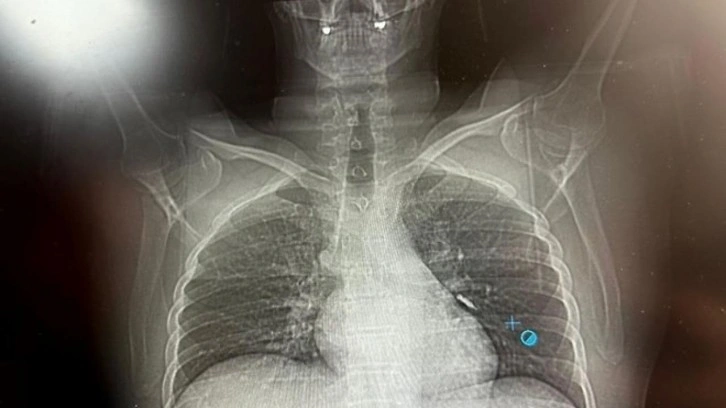

Van'ın İpekyolu ilçesinde ikamet eden F.T. isimli hasta, dış merkezli bir diş kliniğinde implant tedavisi gördüğü sırada, implant vidası yanlışlıkla soluk borusuna kaçtı.

Nefes borusuna kaçan vida nedeniyle hasta, ileri tetkik ve tedavi amacıyla Van Eğitim ve Araştırma Hastanesi'ne sevk edildi.

Hastaya bronkoskopi işlemi uygulandı. Sol akciğerin üst lobunda saplanmış şekilde tespit edilen vida, vidalı yapısı ve bulunduğu konum nedeniyle güçlükle yerinden oynatılabildi.

Yapılan uzun ve titiz müdahale sonrası vida yerinden çıkarılamasa da hasta bir süre sonra geçirdiği öksürükle birlikte implant vidasını midesine gönderdi. Vida, daha sonra doğal yollarla vücuttan atıldı.